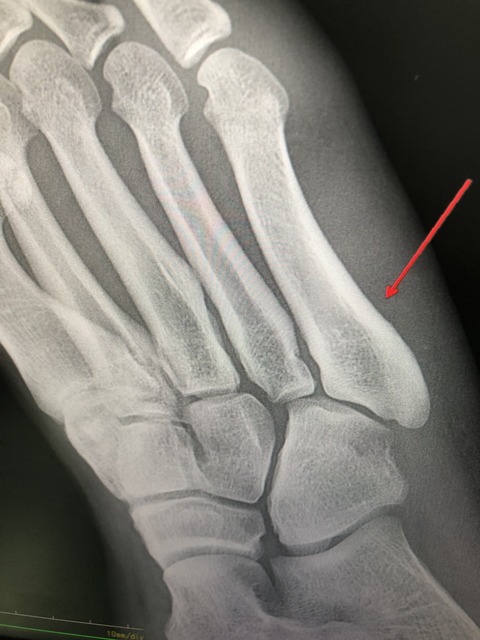

都市対抗 野球リーグが始まります

そんな中、リーグ選手が足を痛め、

来院されました

16BB68AF-3CB2-4BC7-A9F3-106F80CA3137

名捕手であり、何とか、トレーナーと相談の上

出場させる予定です